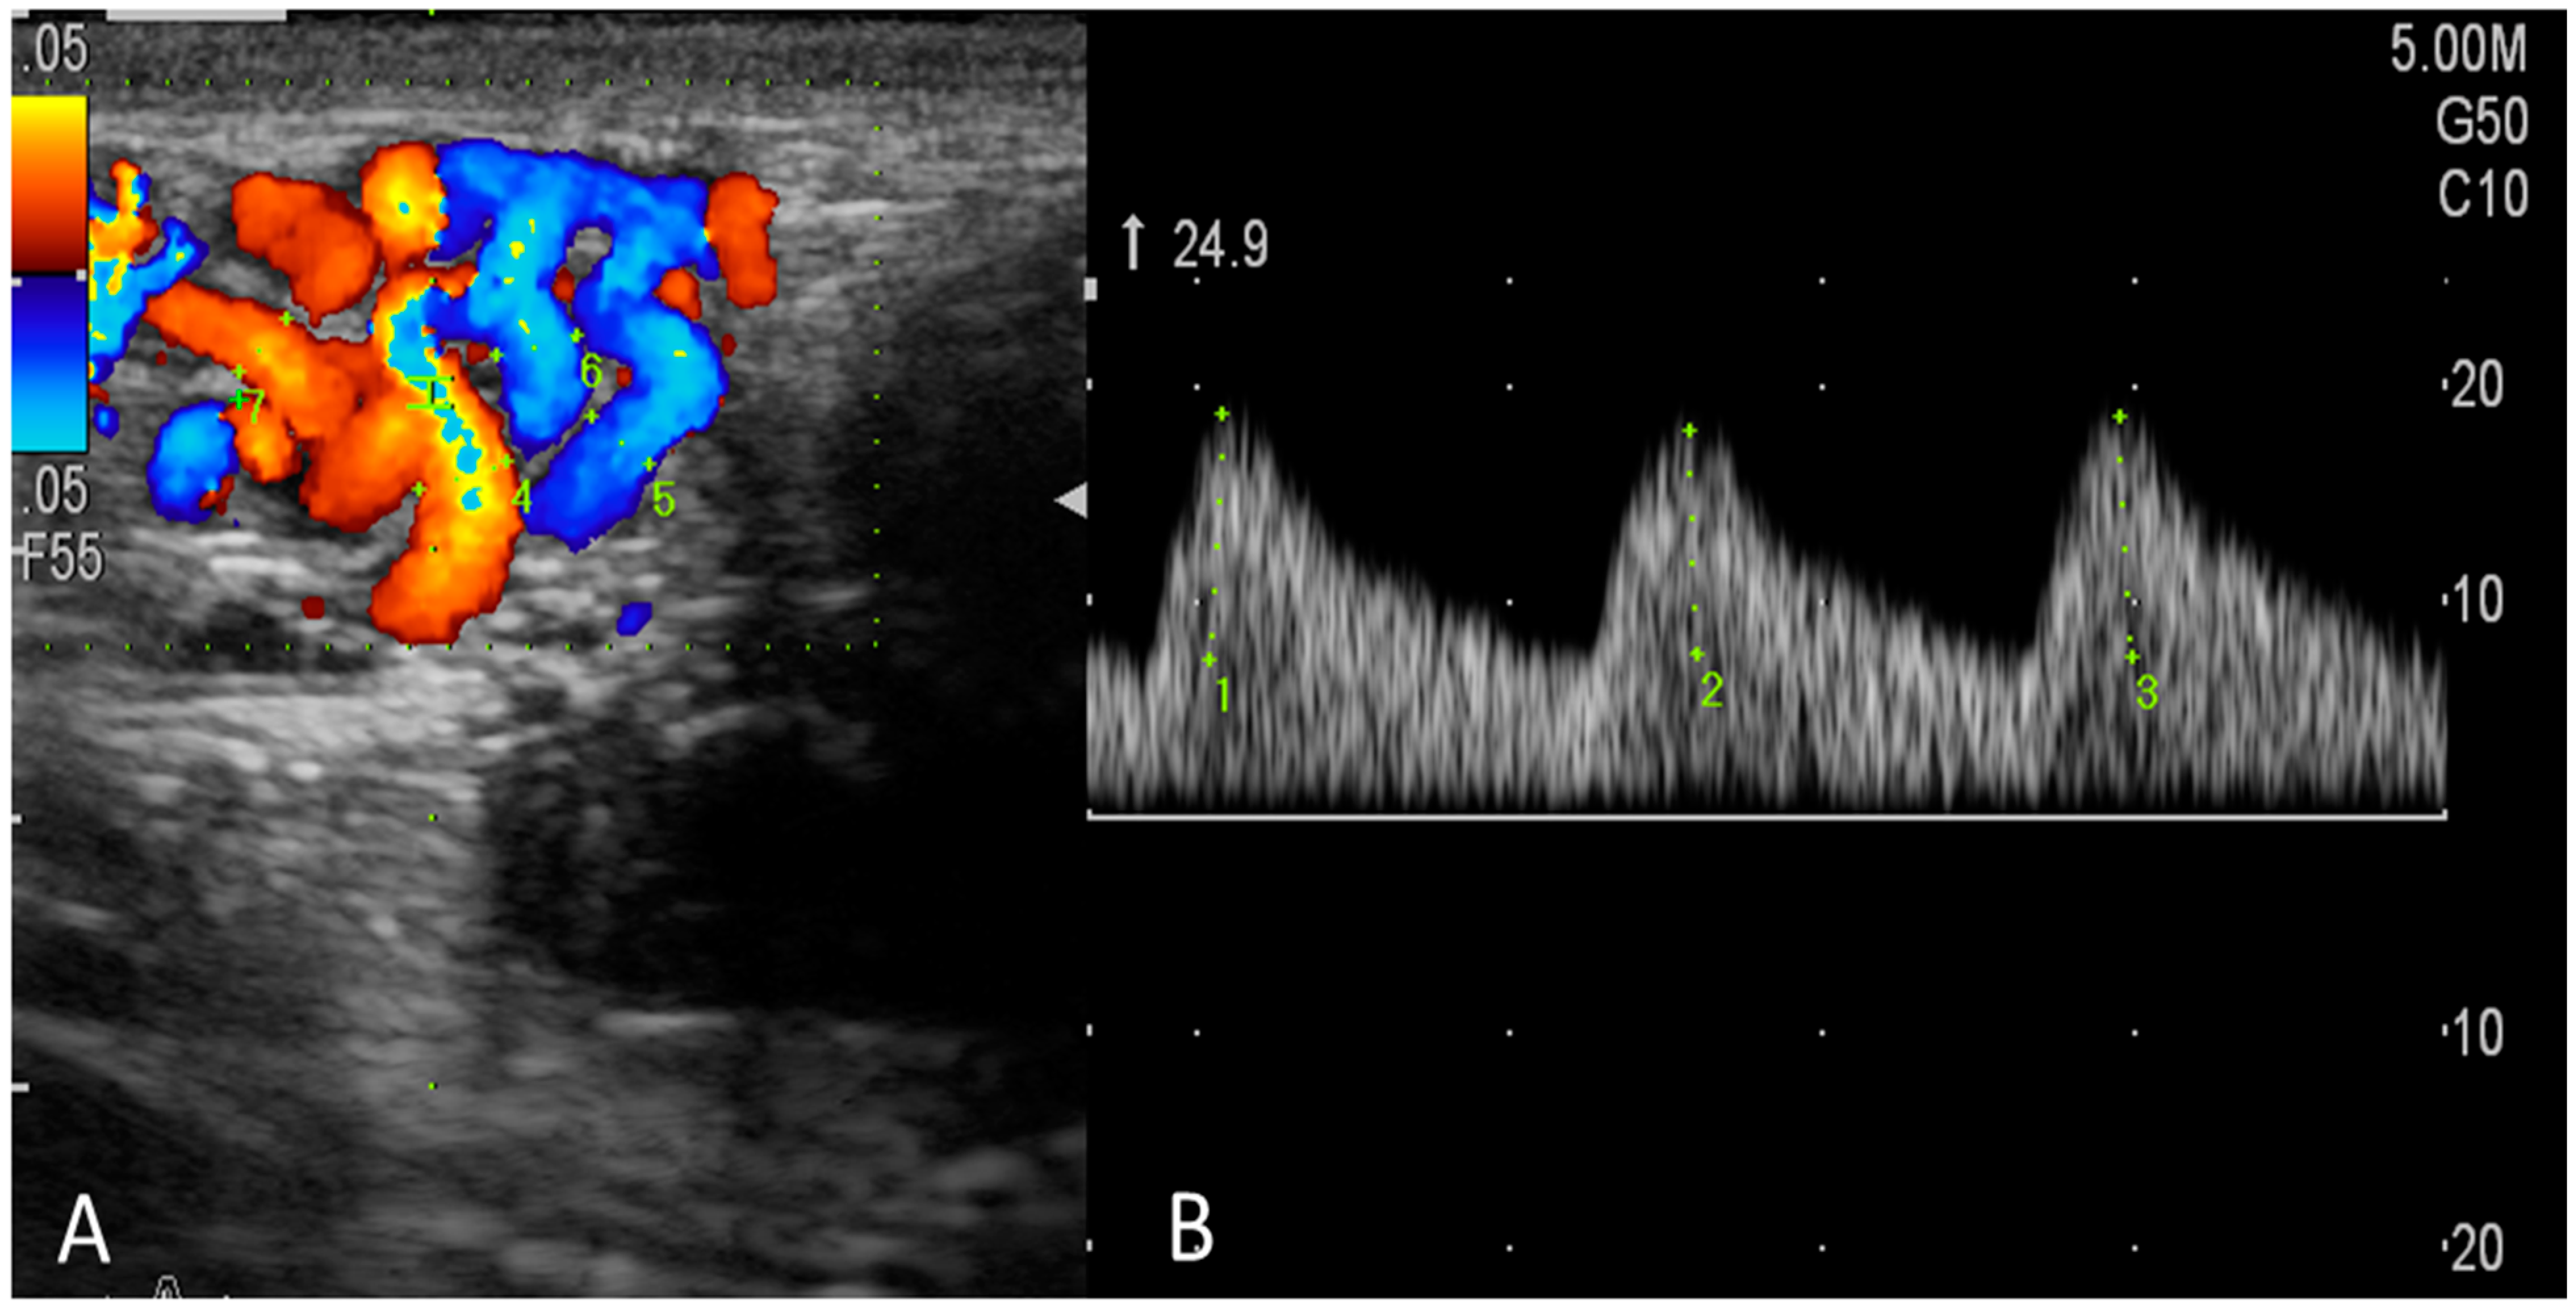

Testicular artery blood flow (TBF) was monitored by the same operator (the first author) using a triplex ultrasound scanner (a ProSound F75 premier CV ultrasonography system; Hitachi Aloka Medical, Tokyo, Japan) that was equipped with an abdominal linear multi-frequency array transducer [6–14 MHz; probe (LN5415)]. As previously described [5,29], the bucks were simply secured, the hairs on both sides of the scrotum were removed via shaving, and a copious amount of ultrasonic gel was applied to the transducer to facilitate the assessment by ultrasonography. In the present study, we monitored testicular artery hemodynamics in supra testicular arteries (STA). After the vascular structures were identified and the largest longitudinal or oblique section of the STA was observed using B-mode ultrasonography, an assessment of TBF was carried out by color-pulsed Doppler ultrasonography as described previously [29,30] in goats. After the appearance of the spectral pattern of the STA (Figure 2), appended parameters were assessed: peak systolic velocity (PSV, cm/sec), end-diastolic velocity (EDV, cm/sec), and the time-averaged maximum velocity (TAMAX, cm/sec). Doppler indices studied were the resistive index (RI = (PSV − EDV)/PSV) and pulsatility index (PI = (PSV − EDV)/time average flow velocity). In addition, total arterial blood flow volume (TABFV) was measured using this equation [31]: TABFV = Cross-sectional area of the examined artery (A) × time-averaged velocity (TAV). In which A = D2 × 0.785; D is the radius (half of the diameter) of the examined artery. The diameter can be measured using the electronic caliber of B-mode ultrasonography. All spectral-Doppler settings (gains, focus, brightness, and contrast) were fixed and standardized. The angle between the long axis of the examined vessel and the Doppler beam was less than 60 degrees in the direction of blood flow, and the depth used ranged from 0.6 to 0.8 cm. The high-pass filter and the Doppler gate were set constant at 50 Hz and 1.5 m, respectively.

Figure 2. Imaging the testicular artery (at the supratesticular region, STA) by color Doppler ultrasonography (A) and the blood flow within the STA appeared as a spectral wave pattern of the testicular artery blood flow with a wave-like display (B).